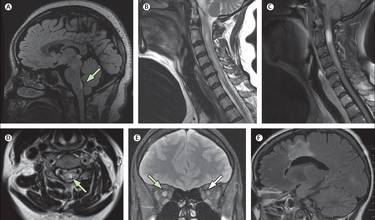

Neuromyelitis Optica (NMO)

NMO er en sjælden autoimmun lidelse, som påvirker synsnerverne og rygmarven. Dette betyder, at man kan opleve nedsat syn og problemer med arme og ben.

Da NMO rammer synsnerverne og/eller rygmarven, har dette betydning for de symptomer, som ses ved NMO. Disse inkluderer eksempelvis: